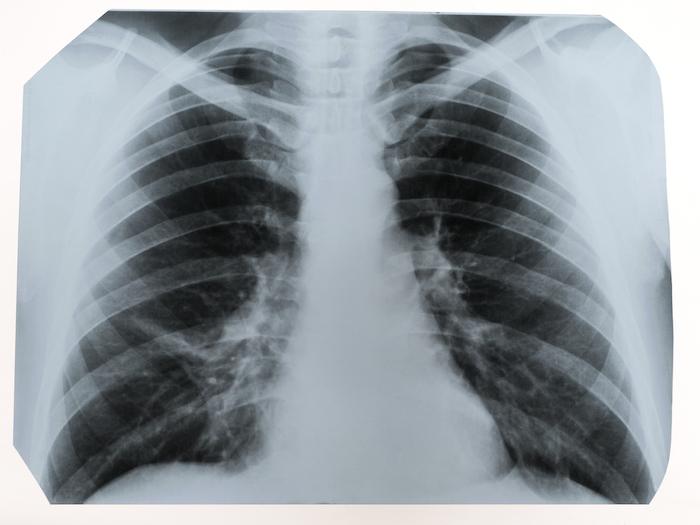

Deux ans s’étaient écoulés entre cette greffe, et l’admission de la patiente de 39 ans au centre hospitalier de Montpellier (Hérault), après qu’une radio des poumons a mis en évidence des foyers suspects, se révélant être une tumeur cancéreuse particulièrement agressive.

"Le traitement immunosuppresseur du receveur a induit un taux de croissance accéléré de la tumeur primaire et des métastases", indique Lung Cancer, affirmant qu’il s’agissait d’un "cancer pulmonaire non à petites cellules". Autrement dit, les poumons de la donneuse, agée d’une cinquantaine d’année, était sains lors de la greffe, malgré le fait qu’elle ait été une grosse fumeuse, consommant un paquet de cigarettes quotidien pendant trente ans.